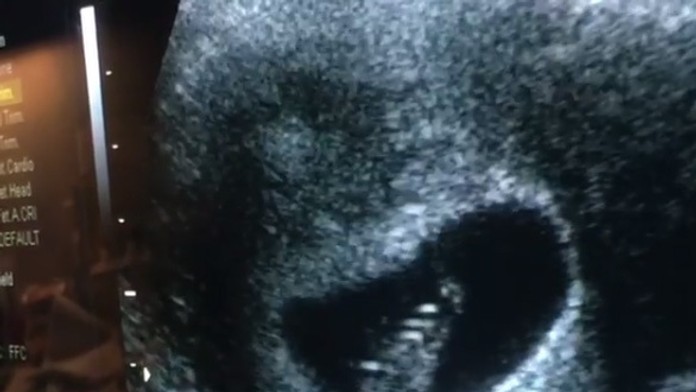

Mara dokonca našla odvahu na to, čo by asi iné zdrvené matky nezvládli. Na Instagrame zverejnila video z lekárskej kontroly. Na záberoch je vidieť dieťatko a lekár im oznamuje, že mu nebije srdiečko. Mnohí ju za to zrejme odsúdia, ale pravdepodobne je to jej spôsob, ako sa vyrovnať so stratou dieťaťa.